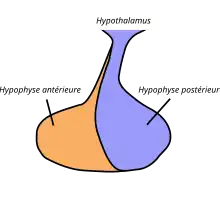

L'hypophyse est divisée en deux lobes : l'antéhypophyse (adénohypophyse) en avant, et la posthypophyse (neurohypophyse) en arrière. L'adénohypophyse dérive du plafond de la cavité buccale primitive (stomodeum), tandis que la neurohypophyse est une extension de l'hypothalamus, relié à celui-ci par la tige pituitaire, et contient les axones de neurones dont les corps cellulaires se trouvent dans l'hypothalamus. On peut également trouver entre l'antéhypophyse et la posthypophyse, une troisième structure, l'hypophyse intermédiaire, bien développée chez certaines espèces animales[Lesquelles ?] : chez l'humain, l'hypophyse intermédiaire (pars intermedia) est seulement visible en période fœtale et jusqu'à l'âge de dix ou vingt ans ; chez l'adulte, il subsiste quelques structures kystiques (follicules, restes de la poche de Rathke), ainsi qu'un infiltrat chromatophile basophile.

Antéhypophyse

L'antéhypophyse (aussi appelée adénohypophyse ou lobe antérieur, pars distalis) contient de nombreux types cellulaires différents qui sécrètent chacun une ou plusieurs des hormones suivantes :

L'antéhypophyse est en relation avec l'hypothalamus et les relations sanguines entre les deux glandes se font par le biais du système vasculaire porte hypothalamo-hypophysaire, qui permet le transport des neurohormones sécrétées par l'hypothalamus. Elle entre donc en jeu dans plusieurs axes de signalisations biologiques, comme l'axe gonadotrope.

Posthypophyse

La posthypophyse ou neurohypophyse (ou lobe postérieur, pars nervosa) est en fait une projection de l'hypothalamus, elle consiste en une agglomération d'axones projetés par les noyaux contenant les corps cellulaires des neurones. Ces neurones sont en contact (par leur cylindraxe) avec des capillaires sanguins entrant par l'artère hypophysaire inférieure et sortant par la veine hypophysaire. Ces bourgeons terminaux axonaux sont dénommés Corps de Herring. Les axones vont sécréter dans ces capillaires sanguins le contenu des granules de sécrétion qu'ils contiennent, qui vont libérer les deux neurohormones qui sont sécrétées au niveau de la neurohypophyse, soit la vasopressine et l'ocytocine. Elle ne produit pas ses propres hormones ; elle ne fait qu'entreposer et distribuer les hormones ocytocine et vasopressine sous forme de neurosécrétions.